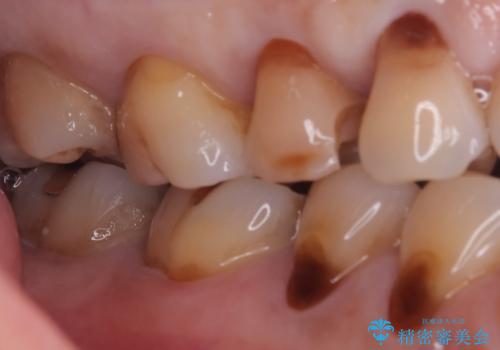

右上5番にう蝕があり、審美性・適合性・材料安定性の高いセラミックインレーでのやり替えとなりました。

右上5番の近遠心にう蝕が認められたため、CR裏層の後MOD窩洞のセラミックインレーとしました。

インレーセット時はラバーダム防湿を行っています。